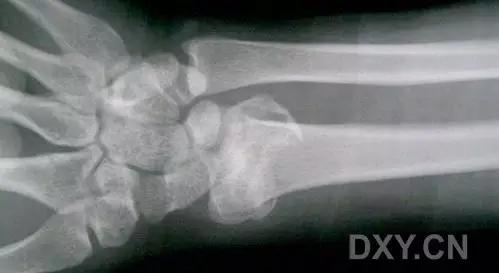

8. Segond 骨折和反向 Segond 骨折

(1)Segond 骨折

是发生在胫骨平台外侧的垂直撕脱性骨折。这种骨折在前后位 X 线片上显示最佳。屈曲位时膝关节受到内旋*力暴**作用,导致皮质骨撕脱性骨折,这种骨折常发生在运动员身上。

常引起股骨内髁和胫骨平台后内侧骨挫伤,75%~100% 的患者伴前交叉韧带断裂,33% 的患者伴外侧半月板损伤。

一位足球运动员的 Segond 骨折。A 正位片示关节线下方胫骨外侧皮质撕脱(箭头)。B MRI 冠状位 T1 加权像示附着于髂胫带的骨折碎片(空箭头)(来源:Radiol Clin N Am 53 (2015) 737–755,YU,Ohio)

(2)反向 Segond 骨折

胫骨平台内侧皮质骨撕脱性骨折,被称为内侧 Segond 骨折或反向 Segond 骨折。这种骨折的旋转机制与 Segond 骨折相反,该骨折与后交叉韧带断裂及内侧半月板损伤相关。

一位足球运动员的反向 Segond 骨折。A 正位片示关节线处的胫骨内侧见一细小骨折片(箭头)。B MRI 冠状位 T1 加权像示骨折片出现在内侧副韧带关节囊附着处(方框)(来源:Radiol Clin N Am 53 (2015) 737–755,YU,Ohio)